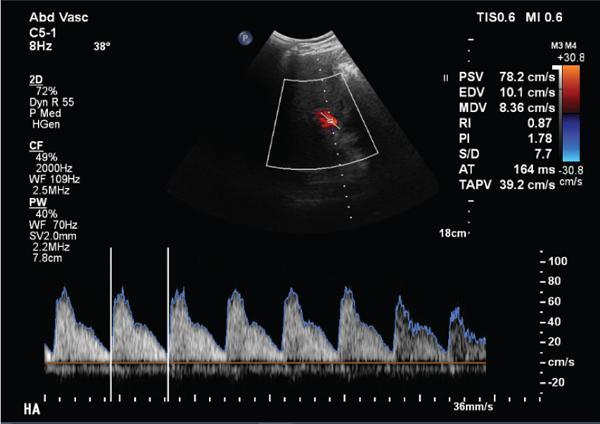

Shrinivas B. Desai, Ritu K. Kashikar, Aman Snehil, Ajay Jhaveri Cirrhosis is a late stage of irreversible scarring of the liver causing abnormality in liver structure and function. Multiple conditions and factors can cause repeated liver damage and scarring ultimately leading to cirrhosis. The most feared complication of liver cirrhosis is the development of hepatocellular carcinoma (HCC). Portal hypertension (PHT) is seen with a variety of conditions but cirrhosis happens to the most important cause. Imaging plays a vital role in noninvasive diagnosis and treatment planning of both cirrhosis and PHT. Liver imaging reporting and data system (LI-RADS) is a standardized reporting system assigning an observation risk of representing HCC. This chapter focuses on discussing aetiologies and imaging of PHT with a lucid review of L1-RADS 2018 version. The portal blood circulation is a unique circulatory circuit as it connects two capillary beds between the liver parenchyma at one end and the gastrointestinal tract and splenic parenchyma at the other end. The portal system ramifies in the liver and ultimately ends in the hepatic sinusoids from where the blood ultimately drains into the inferior vena cava (IVC). The portal vein (PV) originates from the capillary beds in the stomach, intestine and the spleen. The main PV is formed behind the neck of the pancreas by the confluence of the superior mesenteric vein (SMV) and splenic vein. It continues to the porta hepatis where it bifurcates into the left and right branches as it carries nutrient rich but oxygen poor blood to the liver (Fig. 9.9.1). The PV makes up for 75%–80% of the liver’s blood supply while the hepatic artery which arises from the celiac trunk makes up for the remaining 25%. A pathological increase in the portal venous pressure is referred to as PHT. PHT is most often a sequel of chronic parenchymal liver disease and leads to major life-threatening complications due to bleeding from the collateral circulation (most commonly oesophageal varices). Direct measurement of portal pressure (PP) is invasive and often not feasible in most patients and thus imaging plays an important role in the diagnosis of PHT and its complications. The normal portal venous pressure ranges between 5 and 10 mmHg, which is the equivalent of 7–14 cm H2O. The normal hepatic venous pressure gradient (HVPG) is the pressure gradient between the PV and the IVC, is typically 1–5 mmHg. Presence of PHT is indicated by a wedged hepatic venous pressure of more than 5 mmHg. Other definitions include a splenic pressure of more than 15 mmHg or an intraoperative PP of greater than 30 cm H2O. The complications of PHT are seen when HVPG is greater than 10 mmHg and hence this value defines clinically significant PHT. Variceal bleeding is seen with a pressure greater than 12 mmHg. In ideal conditions, the portal circuit is a high flow, low resistance circuit as it has to allow substantial flow rates of 700–1000 mL/min to the hepatic parenchyma from the gastrointestinal tract. Anatomical changes in the organization of the hepatic lobule can result in rise in the portal resistance. These can occur in the form of collagen deposition in the space of Disse, fibrotic scars formed due to regenerative nodule (RN) formation, loss of normal elasticity of the endothelium and distal venous thrombosis. Changes in splanchnic haemodynamics due to factors that increase splanchnic blood flow and increase in intrahepatic vascular resistance due to transformation of stellate cells into myofibroblasts also contribute to the increase in PP gradient. In Western countries, alcoholic cirrhosis and viral cirrhosis are the leading causes of PHT and oesophageal varices. The viral causes form majority of cases leading to cirrhosis and PHT in the Far East and Middle Eastern countries while Schistosomiasis remains an important cause in the African countries. Worldwide, nonalcoholic steatohepatitis (NASH) and hepatitis C are the emerging causes of chronic liver disease (CLD) and PHT. PHT can be classified as cirrhotic and noncirrhotic depending on whether it is associated with cirrhosis or not. This distinction is important as noncirrhotic causes like PV thrombosis are at high risk of development of bleeding but tend to have a better chance of surviving a variceal bleed than a patient with decompensated alcoholic cirrhosis due to preserved hepatic synthetic functions in the former. PHT can also be classified on the basis of the location of the pathology into prehepatic, hepatic and posthepatic causes. Hepatic causes can further be divided into presinusoidal, sinusoidal and postsinusoidal. The causes of portal hypertension have been denoted in Table 9.9.1. The direct measurement of the PP by measuring the HVPG is invasive, expensive not readily available in all patients. Thus, imaging plays an important role in the diagnosis of PHT. Various modalities are used for the imaging diagnosis of PHT. Ultrasonography (USG) and Doppler evaluation have the advantage of being inexpensive, readily available and bedside modality (Table 9.9.2). The role of ultrasound and Doppler in imaging of PHT is to: Grey scale imaging is useful in evaluating the splenoportal anatomy. The evaluation should begin with the liver morphology. Signs of cirrhosis like nodularity of the liver surface with relative atrophy of the right lobe and prominence of the left lobe and caudate should be looked for. Hepatic echotexture appears coarse and more echogenic (Table 9.9.3). Increase in portal venous diameter is a sign of PHT (Fig. 9.9.2). Portal venous diameter of more than 13 or 15 mm has low sensitivity for diagnosing PHT of only 40%–12.5%, respectively. Absolute measurement of the portal diameter as a sign of PHT is also fallacious as in presence of collateral circulation or hepatofugal flow; there may actually be a decrease in the PV diameter. Therefore, a more accurate sign is respiratory variation of PV diameter. An increase in PV diameter of less than 20% with deep inspiration has been reported to indicate PHT with a sensitivity of 80% and specificity of 100%. This has been reported to be an accurate indicator of cirrhosis. Hepatic vein straightness, uniformity of vein wall echogenicity and visualization of at least 1 cm segment of the hepatic vein are the parameters used for evaluation. Splenomegaly is defined as bipolar splenic diameter of greater than 12 cm or largest splenic cross-sectional area passing through the hilum of greater than 45 cm2, and occurs secondary to PHT (Fig. 9.9.3). A total of 65%–80% patients with cirrhosis have splenomegaly on ultrasound. Patients with cirrhosis due to viral hepatitis and primary biliary cirrhosis show splenomegaly more frequently than those with alcoholic cirrhosis. This is an accurate sign of PHT. USG is extremely sensitive with respect to detecting subclinical ascites. Perihepatic space is the most usual site of visualization of minimal ascites. In normal subjects, this ratio is approximately 0.07 and a value above 0.1 suggests the diagnosis of PHT with a 95% sensitivity and specificity. The normal spectral waveform of the hepatic artery is a low resistance flow pattern with forward flow in diastole and a resistivity index in the range of 0.5–0.7. In PHT, the resistivity index of the hepatic artery increases with high resistance flow pattern due to increased peripheral vascular resistance. Resistance index (RI) > 0.78 in the intrahepatic branches of the hepatic artery has been reported to have a sensitivity of 50% and a specificity of 100% for the detection of PHT (Fig. 9.9.11). Pulsatility index (PI) > 1.05 suggests severe PHT with a sensitivity of 86% and specificity of 88% (Fig. 9.9.11). Patency of hepatic veins should be evaluated to rule out Budd–Chiari syndrome as a cause of PHT. The normal hepatic venous waveform (HVW) reflects right atrial activity and this results in a triphasic waveform with one positive and two negative waves. In PHT, this waveform becomes monophasic or biphasic. A monophasic HVW has a sensitivity and specificity of 74% and 95%, respectively, in the diagnosis of severe PHT (Fig. 9.9.12). Dilatation of the splanchnic veins – the SMV and the splenic vein – more than 11 mm are suggestive of PHT with a sensitivity and specificity of 72% and 100%, respectively. A reduction in the respiratory variation of the splenic vein and SMV to less than 40% had a sensitivity and specificity of 79.7% and 100%, respectively, for the diagnosis of PHT (Fig. 9.9.13). The splenic artery reveals an increase in the resistivity index and an RI of >0.63 and a PI of >1 have a sensitivity and specificity of 84.6% and 70.4% for the diagnosis of PHT. Presence of portosystemic collaterals like patent paraumbilical vein, dilated left gastric and short gastric veins are 100% specific sign for PHT (Figs. 9.9.14–9.9.16). Recanalization of the paraumbilical vein, known as the Cruveilhier–Baumgarten syndrome is observed in 43% of patients with PHT, and this is the easiest collateral to assess during the US examination. Various portosystemic collaterals that occur in PHT have been discussed in details in subsection on CT findings in PHT. No Doppler parameter is considered reliable enough to measure PP with sufficient accuracy for use in clinical practice. Oesophageal varices are often present in patients with portosystemic collaterals. Appearance or increase in number of collaterals along with splenomegaly has a high association with variceal formation and growth. USG helps in diagnosis of prehepatic causes like portal stenosis or thrombosis by demonstrating the patency and morphology of the splenoportal system. Arteriovenous fistulae and tumours causing vascular thrombosis as aetiology can be readily detected. USG helps in diagnosis of features of cirrhosis and thus helps differentiate noncirrhotic causes of PHT. USG allows diagnosis of fatty liver disease, which is an emerging cause of cirrhosis. Among the posthepatic causes, USG aids in establishing the diagnosis of Budd–Chiari syndrome by demonstrating the patency and morphology of the IVC and hepatic veins. Owing to the inability of CT to detect flow direction, portal flow rates or pressure gradients, CT is not the primary modality in diagnosis of PHT. Similar to USG dilatation of portosystemic system is a feature of PHT (Fig. 9.9.17). Changes in cirrhosis if present can be seen in the form of surface nodularity, nodules and fibrous septae. CT plays an important role in diagnosis of portal venous thrombosis and evaluating its extent. An acute thrombus is seen as a hypodense filling defect in the vessel causing distension of the venous lumen. Surrounding fat stranding can be seen. A chronic thrombus appears as an eccentric filling defect usually along the wall and is often associated with decrease in vessel diameter. Calcification may be seen in chronic thrombi. Multidetector computed tomography (MDCT) is a useful tool to evaluate portosystemic collateral circulation and recognize complications of PHT. 3D angiography can help understand portal venous and complex variceal anatomy and plan treatment. The various portosystemic collaterals are discussed below. They can be classified into those draining into superior vena cava (SVC) and those draining into the IVC. Magnetic resonance imaging (MRI) is a noninvasive modality used in the evaluation of PHT without the use of ionising radiation. It provides evaluation of parenchymal abnormalities, collaterals and characterization of tumours (Fig. 9.9.28). Spin echo sequences allow characterization of liver masses and liver parenchyma. Loss of flow void allows for detection of thrombosis. Time-of-flight (TOF) angiography is useful in assessing the portal venous system and allows for successful detection of PV thrombosis. The disadvantages of TOF are motion artefacts caused by breathing, long acquisition times and incomplete coverage of the portal venous system. Novel imaging techniques include phase contrast, T1 mapping and magnetic resonance elastography (MRE). The advantage of phase contrast over TOF imaging is that phase contrast imaging acquires information regarding the flow direction in addition to the information regarding the flow velocity. On-phase contrast images signal within vessel is hyperintense when flow is cranial and hypointense when flow is caudal. Look-Locker imaging technique using gradient echo (GRE) MRI sequences with inversion recovery pulse is used to quantify fibrosis by measuring precontrast T1 relaxation times. Interventions in PHT can be aimed at diagnosis or more commonly at management of complications of PHT. HVPG measurement, which is the gold standard for the diagnosis of PHT, can be achieved through cannulation of the PV. Transjugular hepatic biopsy is another diagnostic invasive technique that also allows indirect measurement of PP. Disadvantages include deterioration of hepatic function caused by diversion of portal venous blood flow and shunt dysfunction. TIPSS is contraindicated in patients with congestive heart failure, severe pulmonary hypertension, severe tricuspid regurgitation and hepatic failure. In this technique, a catheter is advanced from the femoral vein into the outlet of the gastrorenal, usually in the region of the left renal vein. The shunt is then occluded with a balloon and sclerosant is injected retrograde to occlude the gastric varices. Histological development of RNs surrounded by fibrous septae in response to chronic liver injury, progressing PHT and end-stage liver disease is termed as cirrhosis. Although initially considered an end-stage phenomenon in CLD, recent evidence suggests that the histological fibrosis can be reversible in early stages with the initiation of specific therapies, for example, in viral cirrhosis with the initiation of antiviral therapy. The one-year mortality rate in cirrhosis varies widely from 1% to 57% depending on the occurrence of complications. Cirrhosis can have a wide variety of causes ranging from congenital to acquired and infectious to noninfectious. It is also a major aetiologic risk factor for the development of HCC. Imaging plays an important role in aetiologic diagnosis of this diverse entity as well as in the diagnosis and management of its complication and surveillance for oncological transformation.